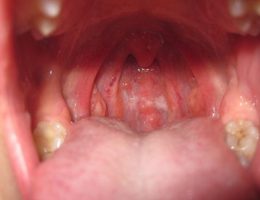

Bác sĩ chuyên khoa chỉ cách nhận biết dấu hiệu sớm của viêm họng hạt

Nếu không thực sự chú ý thì những biểu hiện của viêm họng hạt sẽ dễ bị lu mờ, nhầm lẫn với các bệnh về họng như viêm họng cấp và viêm amidan. Do đó, việc chú ý, phát hiện bệnh sớm sẽ dễ dàng cho việc điều trị và xử lý bệnh càng sớm...